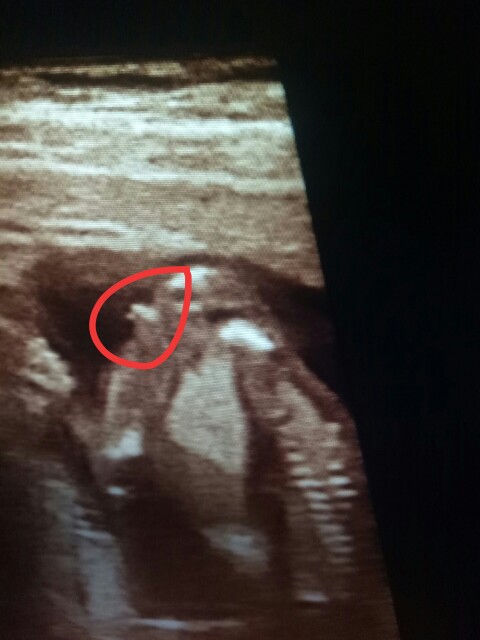

正常胎動和缺氧胎動有什么區別正常胎動和缺氧胎動區別在于胎動變化曲線的規律性、節律性等。正常胎動多少次為標準正常情況下胎動為每小時3~5次,12個小時胎動次數為30~40次。胎動是孕婦感受到胎兒在...